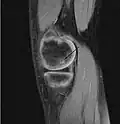

| A large flap lesion in the femur head typical of late stage Osteochondritis dissecans. In this case, the lesion was caused by avascular necrosis of the bone just under the cartilage. | |

Magnetic resonance imaging (MRI) is useful for staging OCD lesions, evaluating the integrity of the joint surface, and distinguishing normal variants of bone formation from OCD by showing bone and cartilage edema in the area of the irregularity. MRI provides information regarding features of the articular cartilage and bone under the cartilage, including edema, fractures, fluid interfaces, articular surface integrity, and fragment displacement.[37][38] A low T1 and high T2 signal at the fragment interface is seen in active lesions. This indicates an unstable lesion or recent microfractures.[30] While MRI and arthroscopy have a close correlation, X-ray films tend to be less inductive of similar MRI results.[38]

Sagittal MRI: Linear low T1 signal at the articular surfaces of the lateral aspects of the medial condyle of the femur confirms the presence of OCD. -